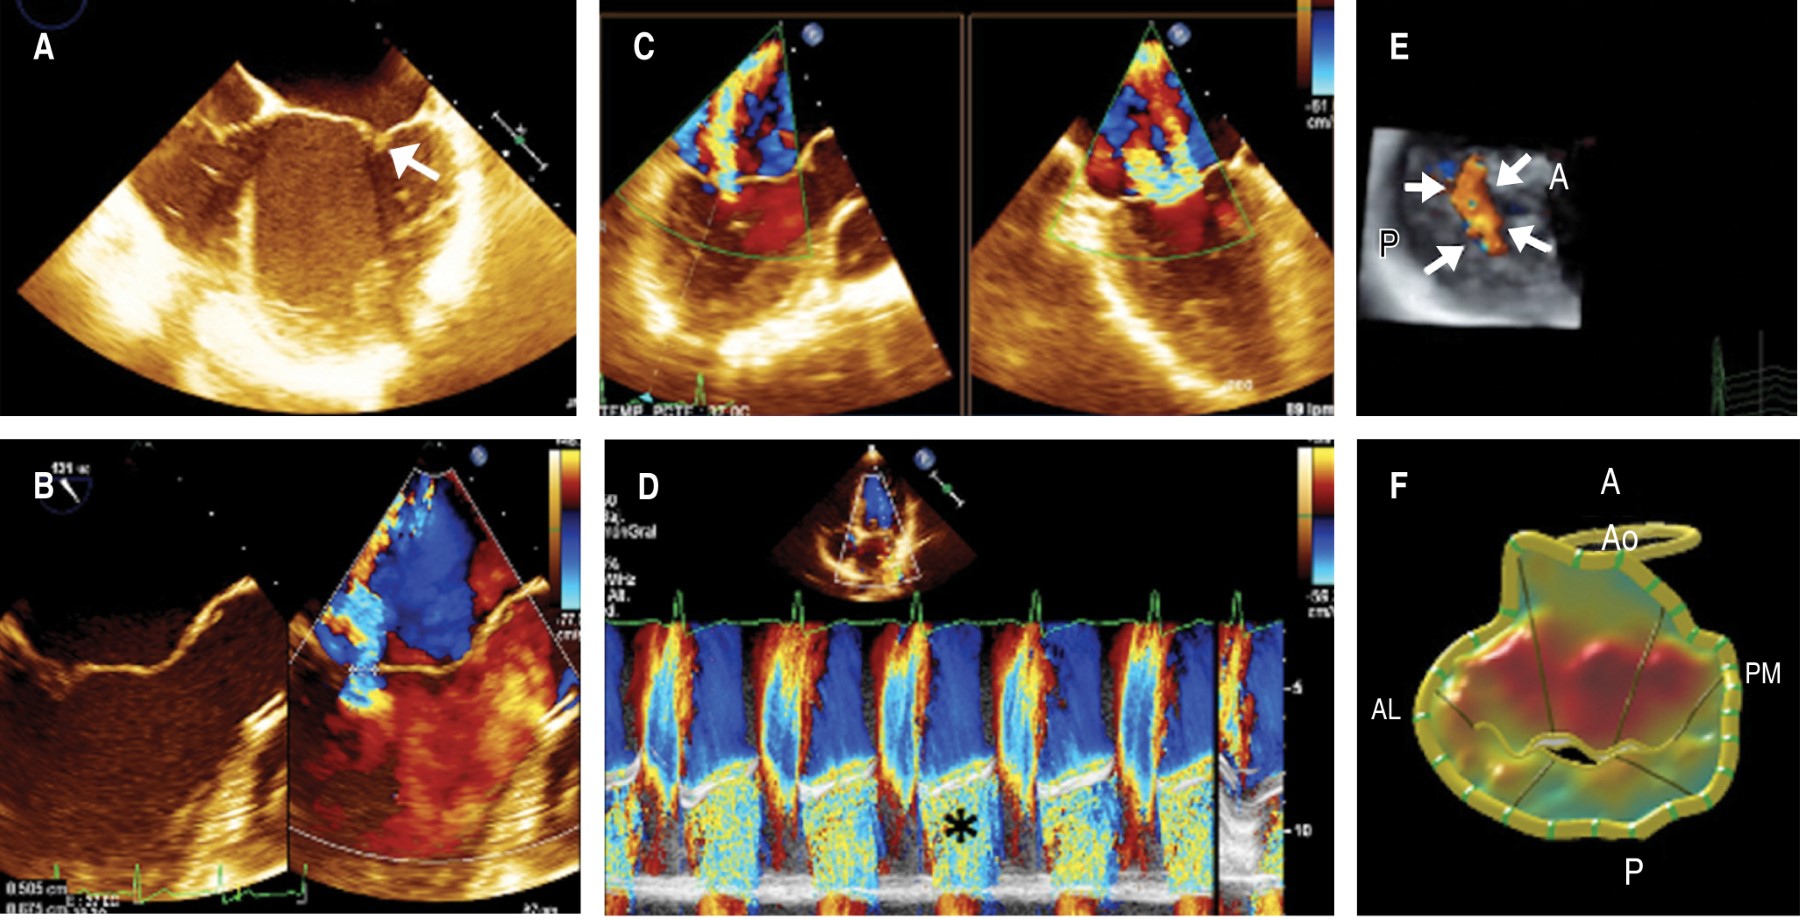

Figura 3